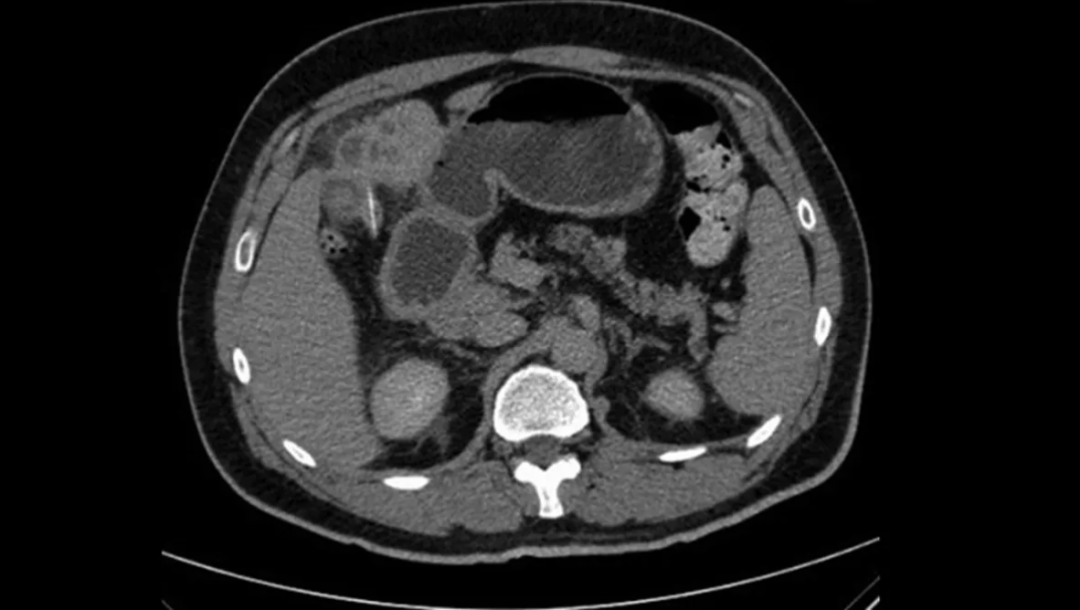

腹部CT显示肝脏IV段有一处边缘强化的不规则低密度灶,大小约5.6×7.5×7.7 cm,与肝脓肿相符。同时,在IV B段肝脏下缘可见一条高密度线状异物,贯穿肝组织,长度约2.5 cm。胆囊形态无异常。胰腺、脾脏、肾上腺和双肾均正常。影像学提示:这是由于肝内异物引起的脓肿。